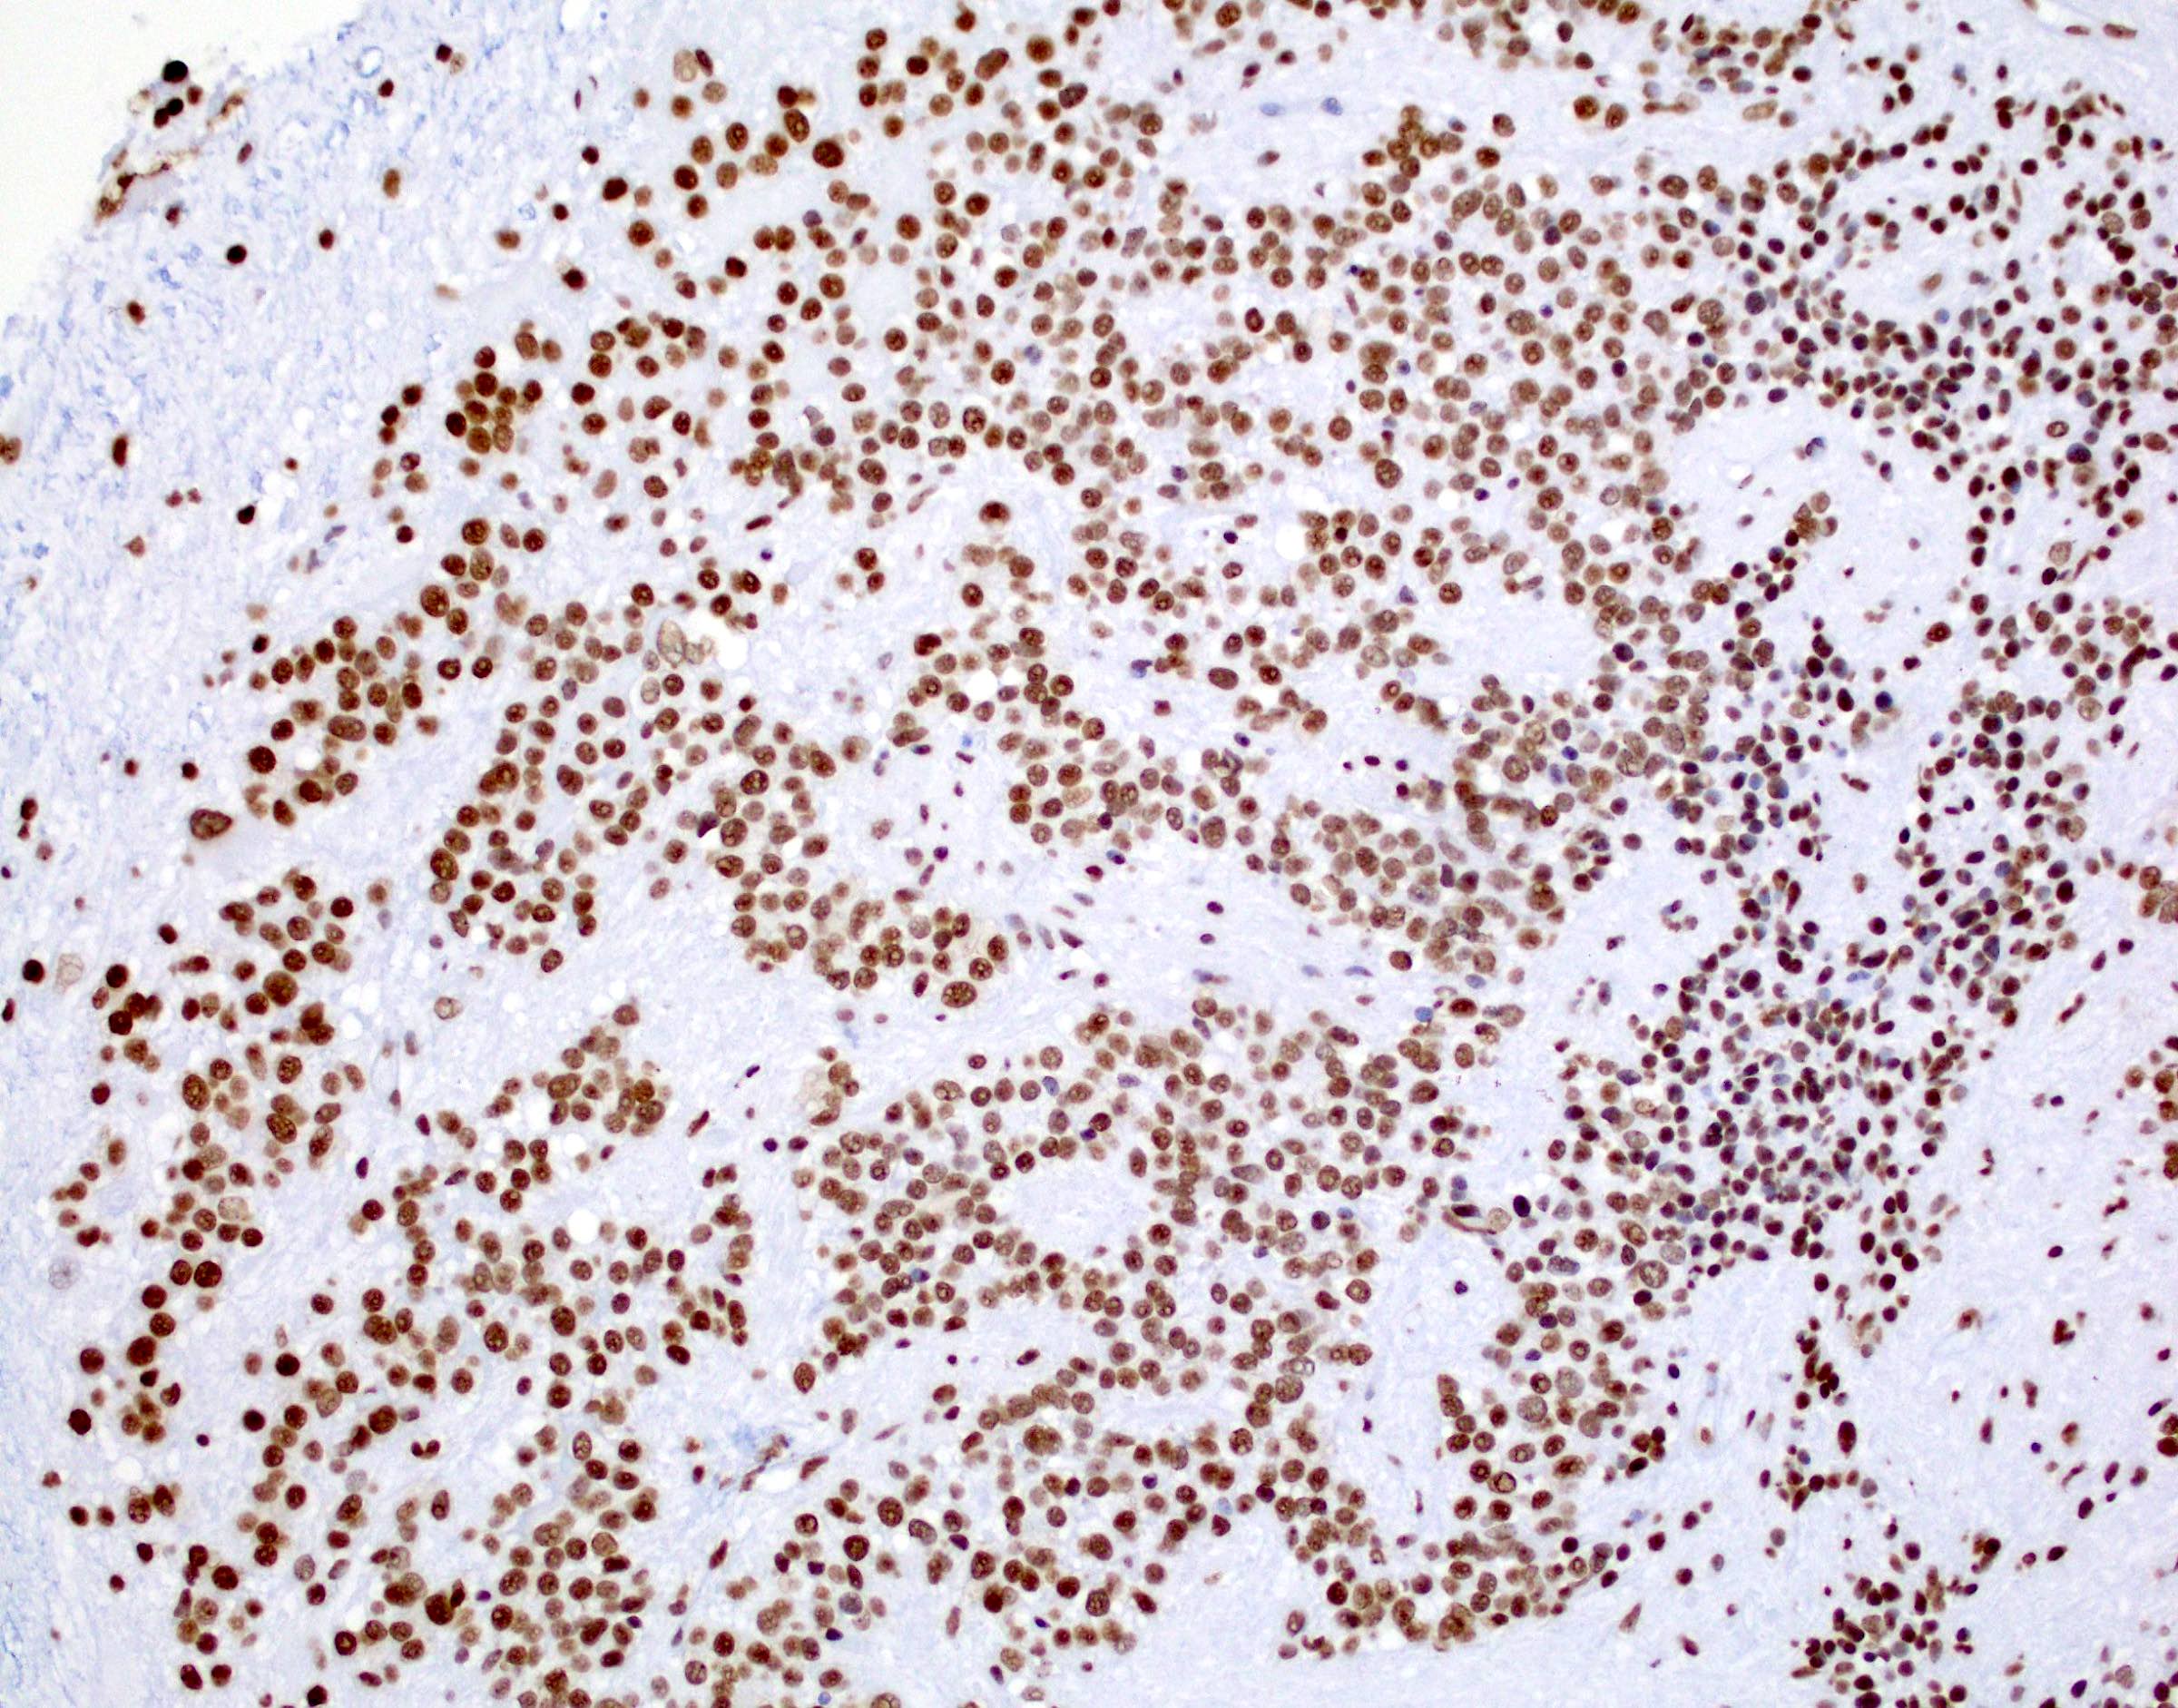

Microscopic (histologic) images

- In posterior fossa ependymomas, decreased expression of H3K27me3 is seen in posterior fossa group A, which has a worse prognosis (Acta Neuropathol 2017;134:705)

- Immunohistochemically, a subset of the tumor cells express GFAP. EMA is negative. MIB1 proliferation index is < 1%. H3K27me nuclear expression is retained in over 95% of tumor cells.

- The collective findings of floor of fourth ventricle location, adult age and retained H3K27me nuclear expression in tumor cells are most consistent with posterior fossa group B (PFB) ependymoma. Correlation with NGS result is recommended.

B. H3K27me3. The H3K27 trimethylation status distinguishes PFA from PFB. PFA has loss of the H3K27 trimethylation and therefore loss of nuclear staining on H3K27me3 staining, while PFB group ependymoma tumor cells have retained nuclear expression. Answers A, C, D and E are incorrect because they do not distinguish H3K27 trimethylation status.